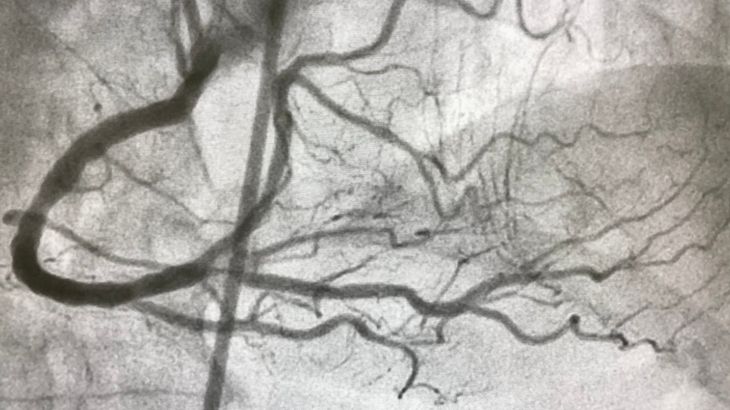

Kronik total oklüzyon (CTO), kalbi besleyen koroner damarların en az üç aydır tamamen tıkalı olması durumudur. Bu tıkanıklık, kalp kasının yeterince kanlanmamasına ve göğüs ağrısı gibi şikayetlere yol açabilir. Kronik total oklüzyon tedavisi, özel ekipman ve deneyim gerektiren ileri düzey bir girişimsel işlemdir. Tam tıkalı damar açma işlemi genellikle kasıktaki ya da bilekteki atardamardan girilerek yapılır. İnce teller ve balonlar kullanılarak tıkalı damara ulaşılır ve damar açılmaya çalışılır. Gerekli durumlarda stent yerleştirilerek damar açıklığı kalıcı hale getirilir.

Kronik total oklüzyon kalp damarlarında en az üç ay boyunca tam tıkanıklığın bulunmasıyla tanımlanabilen klinik bir durumdur. Bu tıkanıklık genelde sertleşmiş, kireçlenmiş plaklardan oluşur ve kan akışını ciddi şekilde engelleyebilir. CTO, koroner arter hastalığı olan bireylerde daha sık görülebilir ve eforla gelen göğüs ağrısı gibi şikayetlere sebep olabilir.

Kronik total oklüzyon (CTO), damarların tamamen ve uzun süredir tıkalı olması nedeniyle standart anjiyo işlemlerine göre çok daha zorlu bir durumdur. Bu tür tıkanıklıklar, damarın iç yapısında sertleşme ve kireçlenmeye yol açtığı için klasik yöntemlerle kolayca açılamaz.

CTO tedavisi, bu nedenle özel teknikler ve deneyim gerektirir. Genellikle bu alanda uzmanlaşmış bir girişimsel kardiyolog tarafından uygulanır. İşlem süresi daha uzun olabilir ve bazen iki farklı damardan aynı anda giriş yapılması gerekebilir. Başarı oranı, kullanılan yöntem kadar işlemi gerçekleştiren ekibin tecrübesine de bağlıdır.

CTO tedavisi özel teknikler ve donanımlar gerektirebilen girişimsel bir kalp ve damar cerrahisi operasyondur. Genellikle perkütan koroner girişim yöntemi kullanılarak tıkalı damar bir tel yardımıyla geçilir ve ardından balon ya da stent ile açılır. Tedavi planı hastanın damar sağlığına, yapısına ve şikayetlerine göre kişiselleştirilebilir.